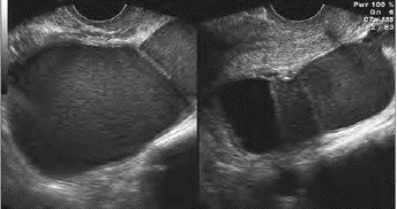

图33-13B 巧克力囊肿(双侧卵巢)声像图

双侧卵巢肿块内均显示密集点状回声及隔带,左侧有部分无回声区